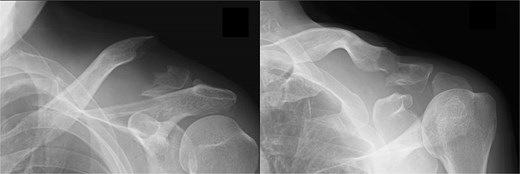

A 66-year-old man presented with left shoulder pain after falling. A Neer Type IIB fracture of the distal clavicle with significant displacement was revealed on radiographs (Fig. 1); however, owing to severe aortic valve stenosis and heart failure, the patient was deemed unfit for surgery. The patient underwent conservative treatment for distal clavicle fracture for 5 months; however, the pain in the left shoulder persisted, and significant skin protrusion caused by a displaced bone fragment was noted. No findings suggestive of neurovascular injury were observed. Radiography and computed tomography (CT) examinations revealed fracture displacement progression (Fig. 2A–C). After undergoing aortic valve replacement 3 months postinjury, the cardiac function of the patient improved and surgery was performed to treat the distal clavicle nonunion.

Radiographs (A and B) and CT scans (C and D) captured after 5 months of conservative treatment show that the displacement has progressed.